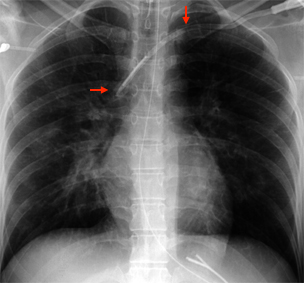

Die weiblich Brust hat die Eigenschaft, im Stehen der Schwerkraft zu folgen, und zwar umso mehr, je schwerer die Brust und je älter die Patientin. Der Port wandert dann mit der Brust nach unten und disloziert den Katheter aus der Vene. An den erweiterten Venen am linken Oberarm und Thorax erkennt man auch eine weitere Komplikation: die Thrombose der Vena subclavia.

Im Röntgen sieht man den dislozierten Katheter und die Kontrastmittelextravasation ins Mediastinum. Dorthin wurde auch das hochgradig gewebetoxische Adriamycin infundiert.